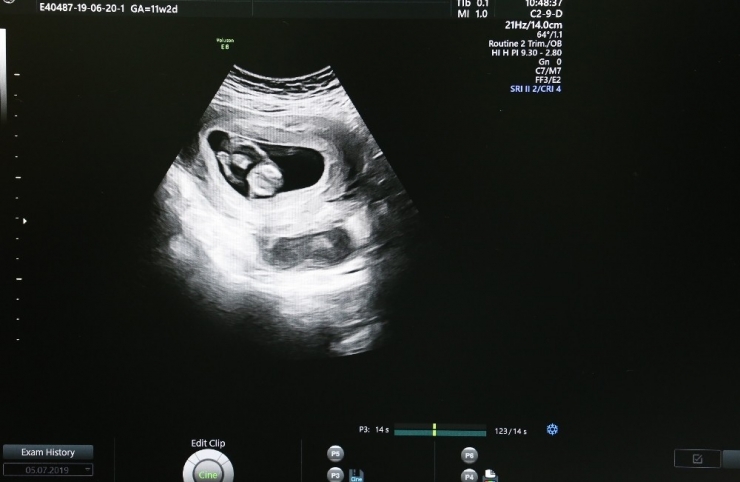

Sivas Cumhuriyet Üniversitesi Araştırma ve Uygulama Hastanesi, riskli gebeliklerin takibini "Ultrasonografi Cihazı" sayesinde kolaylıkla yapılabiliyor.

Sivas Cumhuriyet Üniversitesi Araştırma ve Uygulama Hastanesi, Kadın Hastalıkları ve Doğum Kliniği'nde yaklaşık 1 yıl önce hizmet vermeye başlayan "Ultrasonografi Cihazı" sayesinde anne karnındaki bebeğin bütün yapısal problemleri tespit edilebiliyor.

Cihaz sayesinde anne karnındaki bebeklerde zor ve güç olan problemleri kolaylıkla görüntüleyebildiklerini anlatan Doç. Dr. Çağlar Yıldız, "Bebeğin vücut yapısında bulunan tüm problemleri tespit edebiliyoruz. Örneğin; kalp, beyin gelişimiyle ilgili problemleri, kol ve bacak, yüz deformiteleriyle ilgili problemleri rahatlıkla ortaya koyabilmekteyiz" şeklinde konuştu.